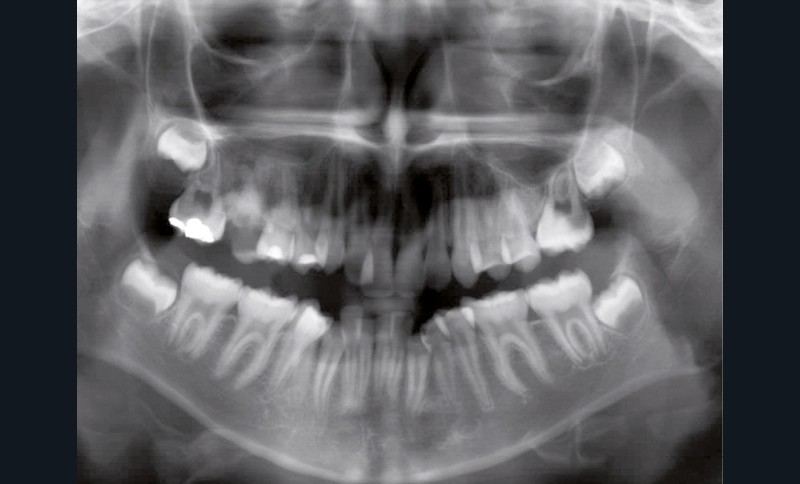

Le niveau d’hygiène est alarmant, car le rituel du brossage des dents n’est pas instauré dans la famille. Des caries se sont développées sur les dents temporaires et en ont imposé l’extraction. Les molaires permanentes ont dérivé mésialement, réduisant l’espace disponible sur l’arcade.

En denture adulte, la DDM est majeure avec un déficit de place estimé de 13 mm à la mandibule. Les lésions carieuses ont aussi touché les premières molaires permanentes maxillaires. La 26 a été avulsée et la 27 a pris sa place. Côté controlatéral, la 16 est fortement délabrée, rendant impossible sa conservation. Les molaires ayant plus mésialé à l’arcade mandibulaire, les rapports occlusaux sont de classe III. Les incisives sont versées vers l’avant, mais nous pouvons considérer qu‘il s’agit d’une biproalvéolie ethnique. Du point de vue squelettique, le patient présente une classe II squelettique par rétromandibulie sur un schéma facial hyperdivergent (fig. 1a-j).